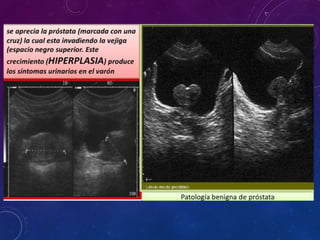

Ecografia prostática via rectal. c, d) largo 64.6 mm, altura 40.9mm) volumen 88.1cc

Ecografia prostática viarectal. c, d) largo 64.6 mm, altura 40.9mm) volumen 88.1cc